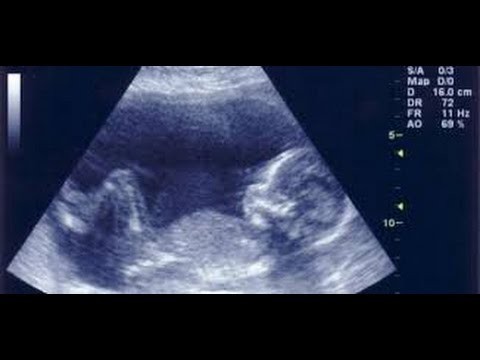

وينبغي على المرأة الحامل عند رغبتها في معرفة نوعية جنينها أن تقوم قبل الإقدام على الكشف بتناول العديد من أكواب المياة مما يساعد على رفع المثانة للرحم مما يسمح للطبيب المتابع للحالة معرفة نوعية الجنين بسهولة من زواية معينة.

إلى جانب إجراء العديد من فحوصات السونار ، إلا أن هناك بعض العلامات التي تشير الى نوعية الجنين و يتم ملاحظتها من خلال حركة الجنين و ما تشعر به الأم ، و من هذه العلامات الآتي:

2-كما أنه في الفحوصات التي يقوم بها الطبيب من خلال السونار ، يلاحظ نمو أعضاء الجنين بشكل أسرع ، إضافة إلى ظهور اليدين والقدمين بسرعة على عكس المتوقع ، الأمر الذي يشير في هذه الحالة إلى أن الجنين ذكر.